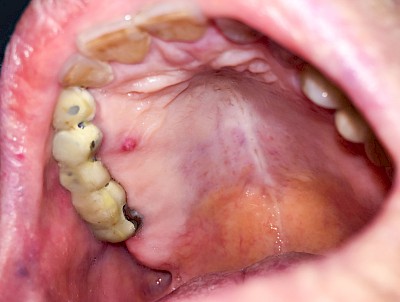

Einschmelzung & Geschwür

Das Risiko für Krebs der Mundhöhlen-Schleimhäute ist bei Menschen, die jahrelang übermäßig viel (Abusus) geraucht und erst recht lange übermäßig viel Alkohol getrunken haben, stark erhöht. Die Schleimhäute sehen dann aus wie "wildes Fleisch" – entweder mit blumenkohlartigen Auftreibungen oder aber es zeigen sich großflächige ungleichmäßig geformte Defekte und Einschmelzungen. Man spricht dann auch von einem Geschwür (Ulcus).

Entsteht der Krebs eher in tieferliegenden Schichten (z. B. im Bereich der Speicheldrüsen), sind die Auffälligkeiten nicht so deutlich. Hier fallen eher Seitenunterschiede links und rechts im Bereich der Mundhöhle auf. Auch plötzlich auftretendes und wiederholtes Nasenbluten, Einschränkungen der Atmung durch die Nase können Anzeichen für einen Tumor im Bereich der Nasen- oder Kieferhöhle sein.

Selten können auch Fibrome oder Druckstellen bei Zahnprothesen, wenn diese nicht erkannt und behandelt werden, in "wildes Fleisch" übergehen und hin zu bösartigen Tumoren entarten.

Bei allen diesen Auffälligkeiten ist eine sofortige (zahn-)ärztliche Abklärung zu veranlassen.